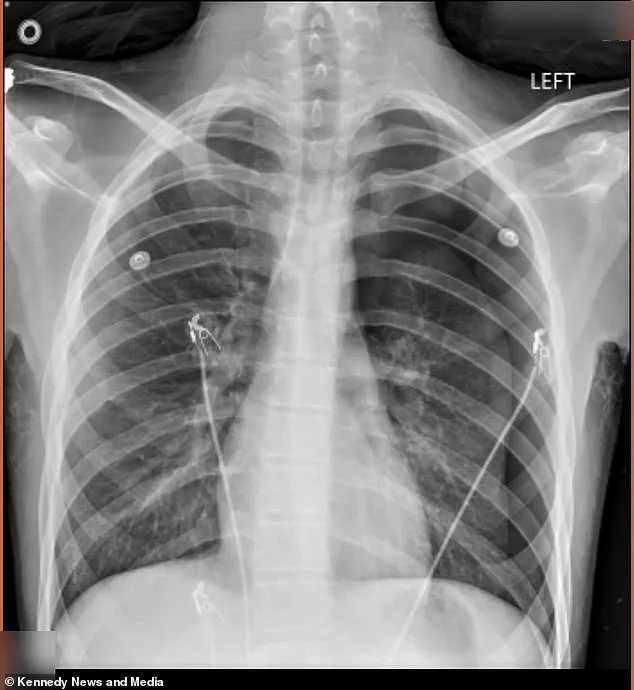

Doctors found 50 percent of his left lung had collapsed. A pneumothorax. Air had seeped into his chest cavity, creating pressure that forced a 18-inch tube into his body to drain the excess. The first collapse was a warning. The second, in January 2026, nearly killed him. 'They said he could have died in the lobby,' Vann said. 'I thought, *Why him?*'"